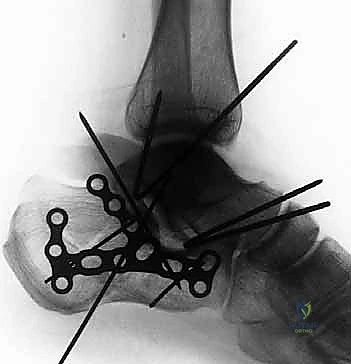

صور إضافية من داخل غرفة العمليات توضح دقة الإجراء

توضح الصور التالية مدى تعقيد الجراحة والدقة التي يتطلبها تثبيت عظم الكعب، والتي يعكسها التميز الجراحي للأستاذ الدكتور محمد هطيف: